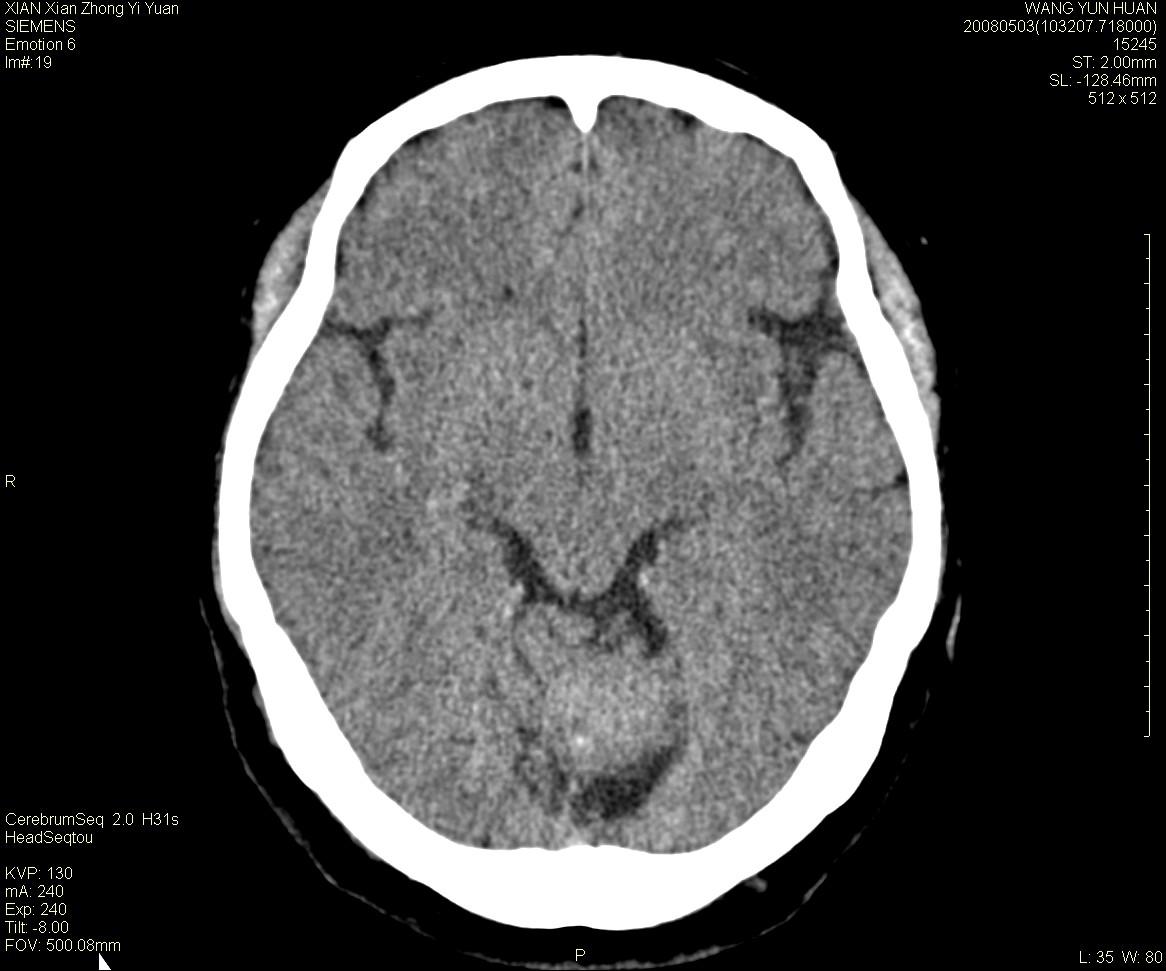

标题: CT13219:(补充强化)请会诊,患者女,60岁,头晕,大家看 [打印本页]

标题: CT13219:(补充强化)请会诊,患者女,60岁,头晕,大家看

病灶显示轻度强化,ct增加4hu左右,大家看是什么肿瘤.

强化后动脉期及延迟2分钟,五分钟图像

小脑蚓部囊型肿块,内有实性结节及钙化点。增强后囊壁及结节轻度强化。

考虑蚓部星形细胞瘤(ⅱ级可能性大)。

小脑蚓部肿块,周围无明显占位效应及水肿带,增强轻度强化,考虑低分级星形细胞瘤。